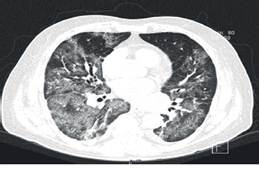

Debido a la sobreexigencia de los servicios médicos y laboratoriales por aquel momento, no se tiene confirmación positiva de la RT-PCR SARS-CoV-2 hasta los 3 días de su admisión intrahospitalaria. Se toman nuevas analíticas de control y en éstas se aprecia notable aumento del dímero-D llegando hasta los 4 360 ng/ml (Ver Tabla. 1). En el contexto de un paciente con progresiva escalación de las medidas ventilatorias con cánulas nasales de alto flujo y bajo la utilización de los índices Rox y Kirby, aunado al aumento de la respuesta inflamatoria sistémica, se sospecha de tromboembolia pulmonar (TEP) versus alguna coinfección o sobreinfección por lo que se solicitan angiografía por tomografía computada (Angio-TC), TC-Tx de control y panel PCR respiratorio. En Angio-TC no se identifican datos sugerentes de TEP, TC-Tx muestra hallazgos compatibles con neumonía producida por SARS-CoV-2 en fase moderada, progresión de la infección en base a última toma de control, atelectasias y consolidaciones bilaterales hacia las bases (Ver Figura. 2 y 3). Panel PCR respiratorio revela la detección del virus Influenza A H1N1.

Este reporte de caso presentado destaca 2 desafíos en el diagnóstico y por lo tanto en el tratamiento conjunto de COVID-19 e Influenza A H1N1. Primero, aunque generalmente la toma de tomografía computada de tórax con el respectivo hallazgo de patrón en vidrio esmerilado junto a la sintomatología clásica de COVID-19 ya mencionada, son aceptables para establecer una sospecha diagnóstica, pueden ser insuficientes en caso de coinfección de Influenza A H1N1. Los hallazgos iniciales tomográficos de este caso no mostraron ningún signo que condujera a la sospecha de alguna coinfección o sobreinfección, ya que sólo mostraron patrón de vidrio esmerilado y empedrados postero-basales, signos característicos de infección por SARS-CoV-2. No fue hasta que el curso de la infección avanzó, y ante la falta de mejoría tanto clínica como analítica del paciente, que se realizó tomografía computada de tórax de control, la cual evidenció la aparición de consolidaciones bilaterales, un hallazgo recurrente en caso de infección por Influenza A H1N1. Por otro lado, una problemática más durante el diagnóstico; fueron las analíticas de sangre con los correspondientes reactantes de fase aguda quienes ante la presencia de ambas entidades patológicas no fueron de utilidad para poder distinguir si la enfermedad de base, en este caso COVID-19, se encontraba acompañada de alguna otra entidad patológica. Sino solo para evidenciar el incremento sostenido de los parámetros inflamatorios.